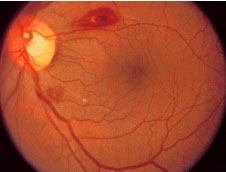

- Nódulos de Roth ☤ en la retina.